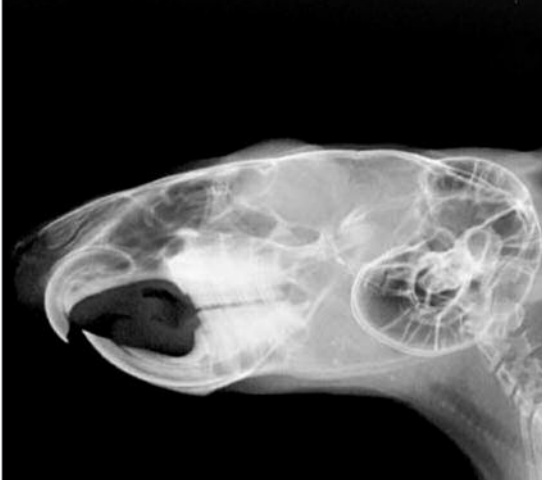

Most common dental pathology of rabbits

A

Malocclusion

What animals are aradicular hyposodont

Rabbit, GP, Chichin